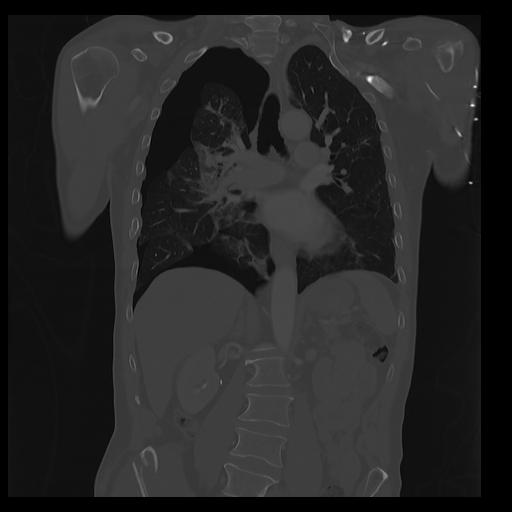

32 PULMON,CE,Coronal,3.000,PULMON,Coronal,